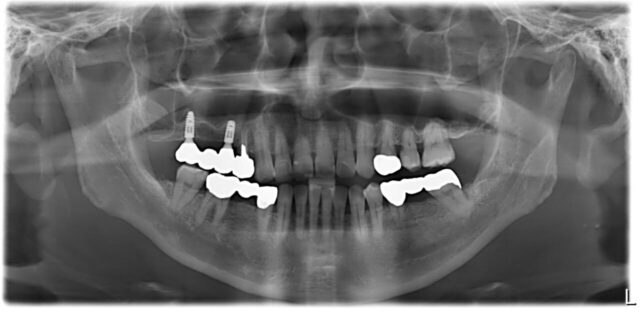

骨隆起を移植したフランク骨造成とインプラント症例

| 治療方法 | 右上6番抜歯,上顎骨隆起を移植したフランク骨造成,インプラント治療 |

| デメリット・注意点 | 歯周病により歯槽骨が崩壊,インプラントの長期安定を目指すため骨移植が必須でした. |

| 備考 | 抜歯後の治癒に2ヶ月. 骨移植後の治癒に6ヶ月. インプラント1次オペ後の治癒に4ヶ月. 治癒を待つ期間が長く,その間に保険で歯周病治療と虫歯治療を行いました. |

上部構造・ジルコニアブリッジ装着